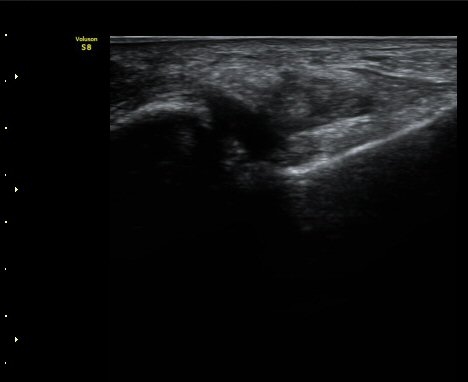

Àü°Å°ñºñ°ñÀδë Á¾´Ü¸é°Ë»ç¿¡¼­ ÀδëÀÇ Àú¿¡ÄÚ ºÎÁ¾ÀÌ °üÂûµÈ´Ù(±×¸² 2).